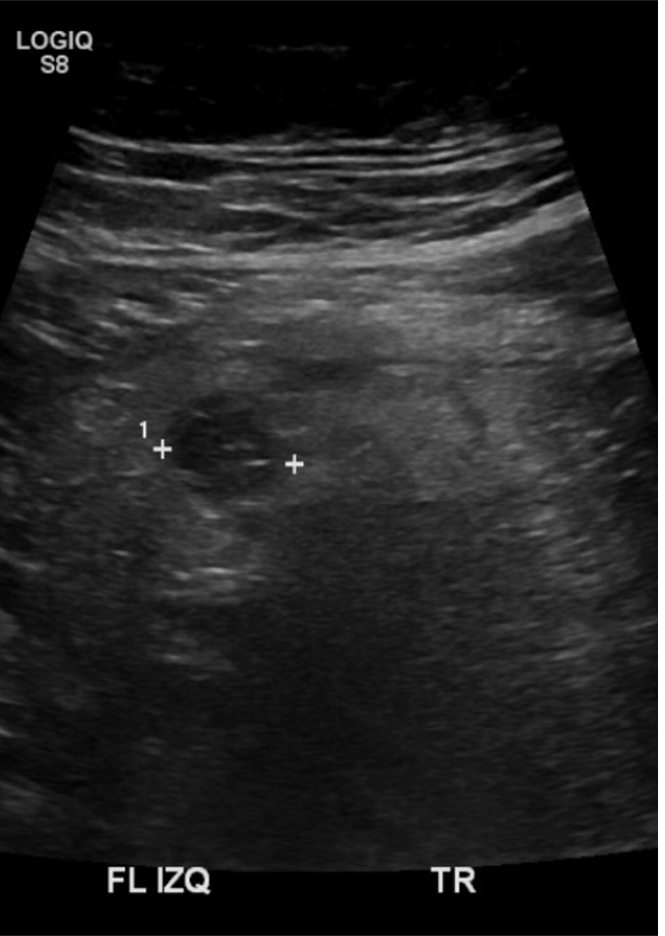

Examen limitado por meteorismo. Páncreas parcialmente visualizado. Hígado aumentado de ecogenicidad con área de respeto periportal sugerente esteatosis difusa moderada. En región dolorosa en FII se observa imagen pseudonodular hipoecogénica, con aumento de ecogenicidad de la grasa adyacente, sin relación intestinal evidente, sugerente apendagitis epiploica.

Hallazgos ecográficos sugerentes de apendicitis epiploica a nivel del flanco izquierdo. Cambios de esteatosis hepática leve. Resto del estudio ecográfico abdominal sin hallazgos significativos.